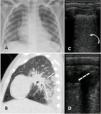

A 16-year-old female homozygous SCD, was admitted at the hospital with 12 h of abdominal, back and leg pain. She was in use of hydroxyurea since the age of six due to multiple episodes of ACS and VOC. The patient received morphine and intravenous fluids and at day 2 presented SpO2 of 88% so nasopharyngeal swab for SARS-CoV-2 was performed. Bilateral basal consolidations were found in the chest radiograph (Fig. 2), ceftriaxone, clarithromycin and supplementary oxygen were initiated. COVID-19 infection was confirmed and chest CT showed consolidations, infiltrates with ground-glass opacities and small pleural effusion on both lungs (Fig. 2). After 72 h of antibiotics she became afebrile but on day 7 and 8 she presented an axillary temperature of 38,5 °C and antibiotics were changed to piperacillin-tazobactam. On day 10 nasopharyngeal swab for SARS-CoV-2 was negative, she was afebrile after day 12 and all blood cultures were negative. She was dismissed after 19 days of hospitalization.

Case 3A seven-year-old boy with hemoglobin SC disease was admitted at the hospital with four days of abdominal and leg pain and dry cough. He reported no fever but was in use of regular ibuprofen and dipyrone for pain control for the last days. He had a past history of asthma which required continuous use of beclomethasone inhalation. At hospital his SpO2 was 90% on room air and he was admitted for supplemental oxygen, ceftriaxone and azithromycin, as well as morphine and intravenous fluids. Nasopharyngeal swab for SARS-CoV-2 was performed and the virus was confirmed by RT-PCR. Chest radiograph showed bilateral patchy consolidations and chest CT showed areas of air space consolidation and ground-glass opacity in association with atelectasis on both lungs; the ultrasonographic findings were coalescent B lines, subpleural consolidations and thickened pleural line on inferior zones of both lungs (Fig. 3). At this occasion d- dimer was 5,99 mcg/mL. At day 6 he became febrile, and on day 8 began salbutamol and dexamethasone for asthma exacerbation. He maintained the need for supplemental oxygen and regular antipyretic, new chest CT showed worse pulmonary images - the consolidations were larger and the distribution of the ground glass opacities were diffuse - and laboratory exams showed platelets of 1.289.000/uL and d-dimer of 7,7 mcg/mL, so enoxaparin and vancomycin were initiated. He later showed epigastric pain, an echocardiogram and a CT pulmonary angiography for thromboembolism protocol were performed, both with negative results. After day 13 he was afebrile and required no more supplemental oxygen. Cultures showed no bacterial growth and nasopharyngeal swab for SARS-CoV-2 was negative on day 23. He completed a total of 24 days of hospitalization.

Panel A (chest radiograph): retrocardiac bilateral peribronchial consolidations. Panel B (sagittal chest CT): peri bronchial patchy consolidations and ground glass consolidations on the left lung. Panel C and D (LUS): multiple B lines erasing A lines and subpleural peripheral consolidation implying alveolar-interstitial syndrome of inferior zones of both lungs.